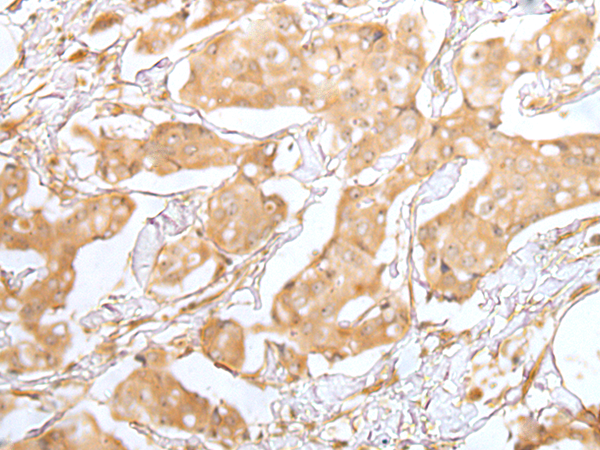

ELISA, IHC

IHC positive control:

Human gastric cancer and human breast cancer